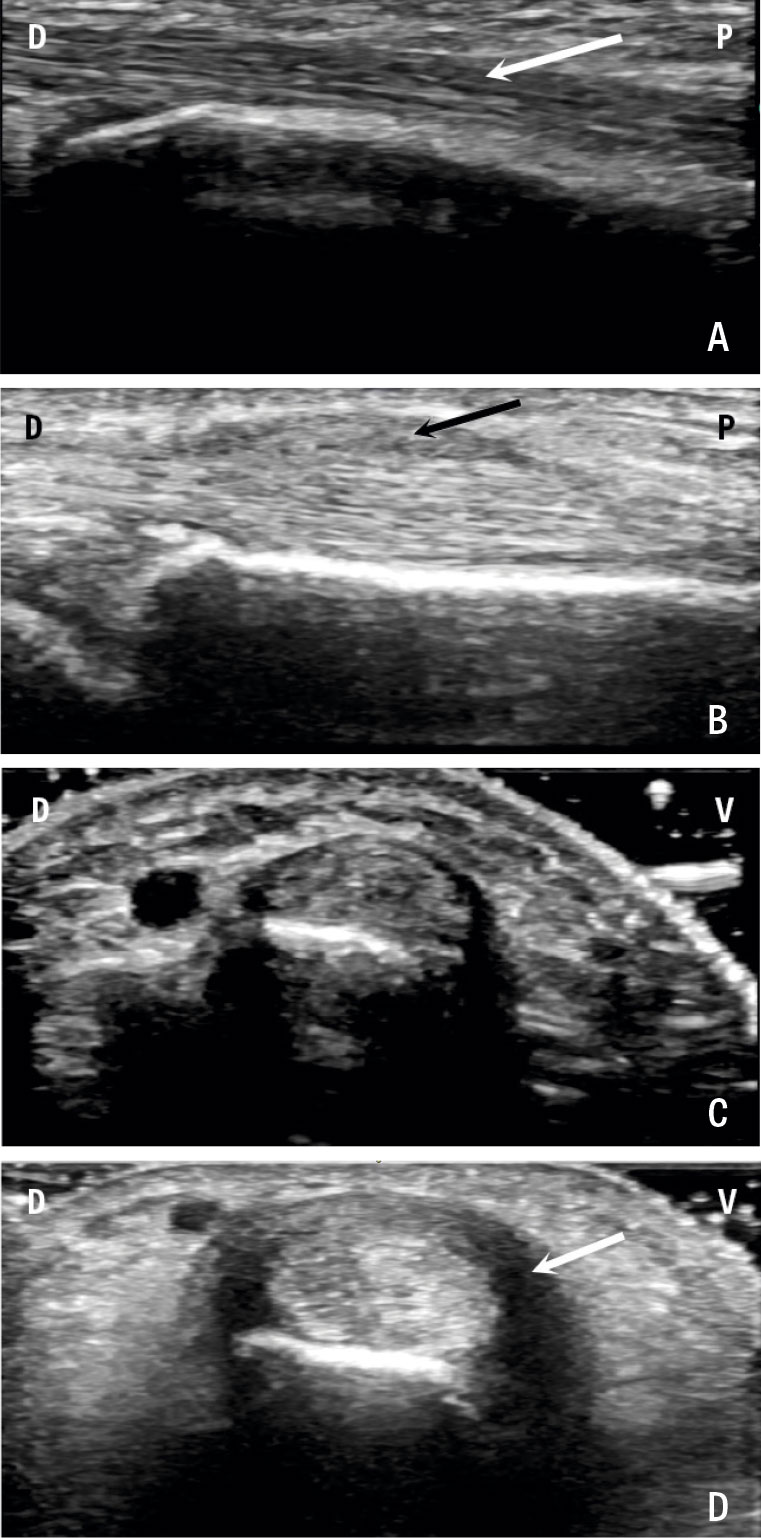

Ultraljudsbild av första dorsala senfacket och musculi abductor pollicis longus (ABL) och extensor pollicis brevis (EPB).

A. Längsgående bild av APL-och EPB-senorna (vit pil) på person utan morbus de Quervain, dorsalt (D) och proximalt (P).

B. Längsgående bild på patient med långt stående morbus de Quervain. Notera förtjockat

retinakel (svart pil) och förtjockad sena.

C. och D. Tvärgående bild av dessa senfack, ventralt (V) och dorsalt (D). Notera den uttalade tenosynoviten (vit pil) på patienten med morbus de Quervain.